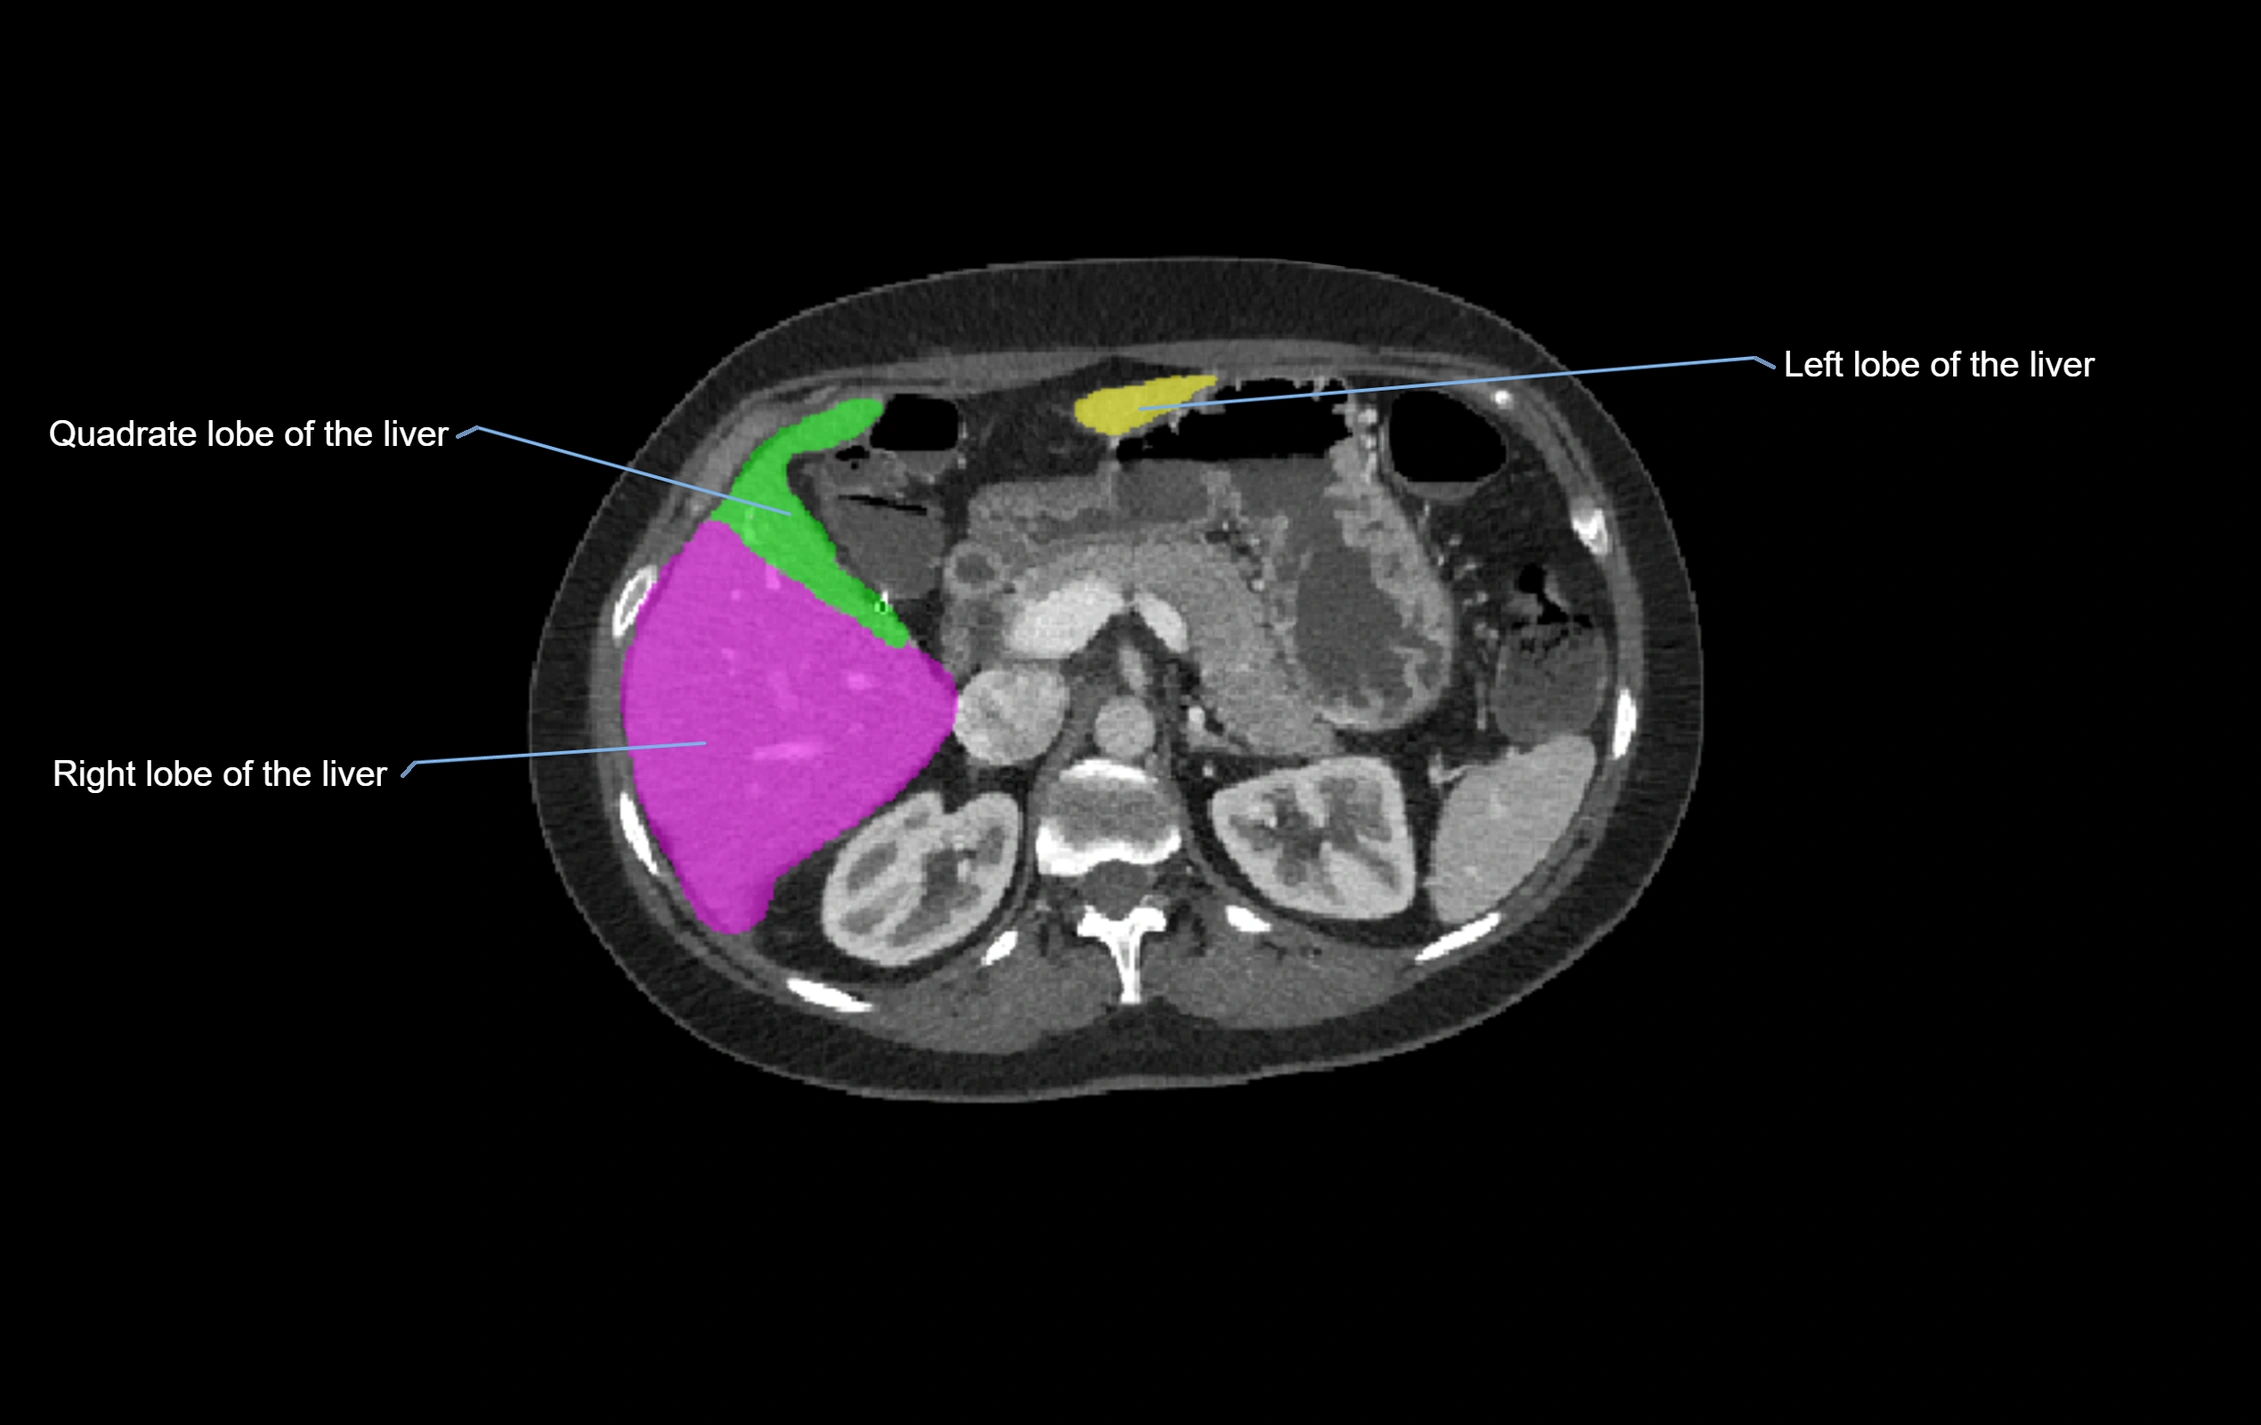

CT Image

image